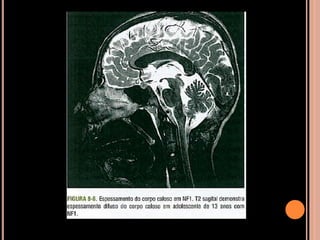

 Espessamento do corpo caloso (atividade anormal

da neurobrimina?)